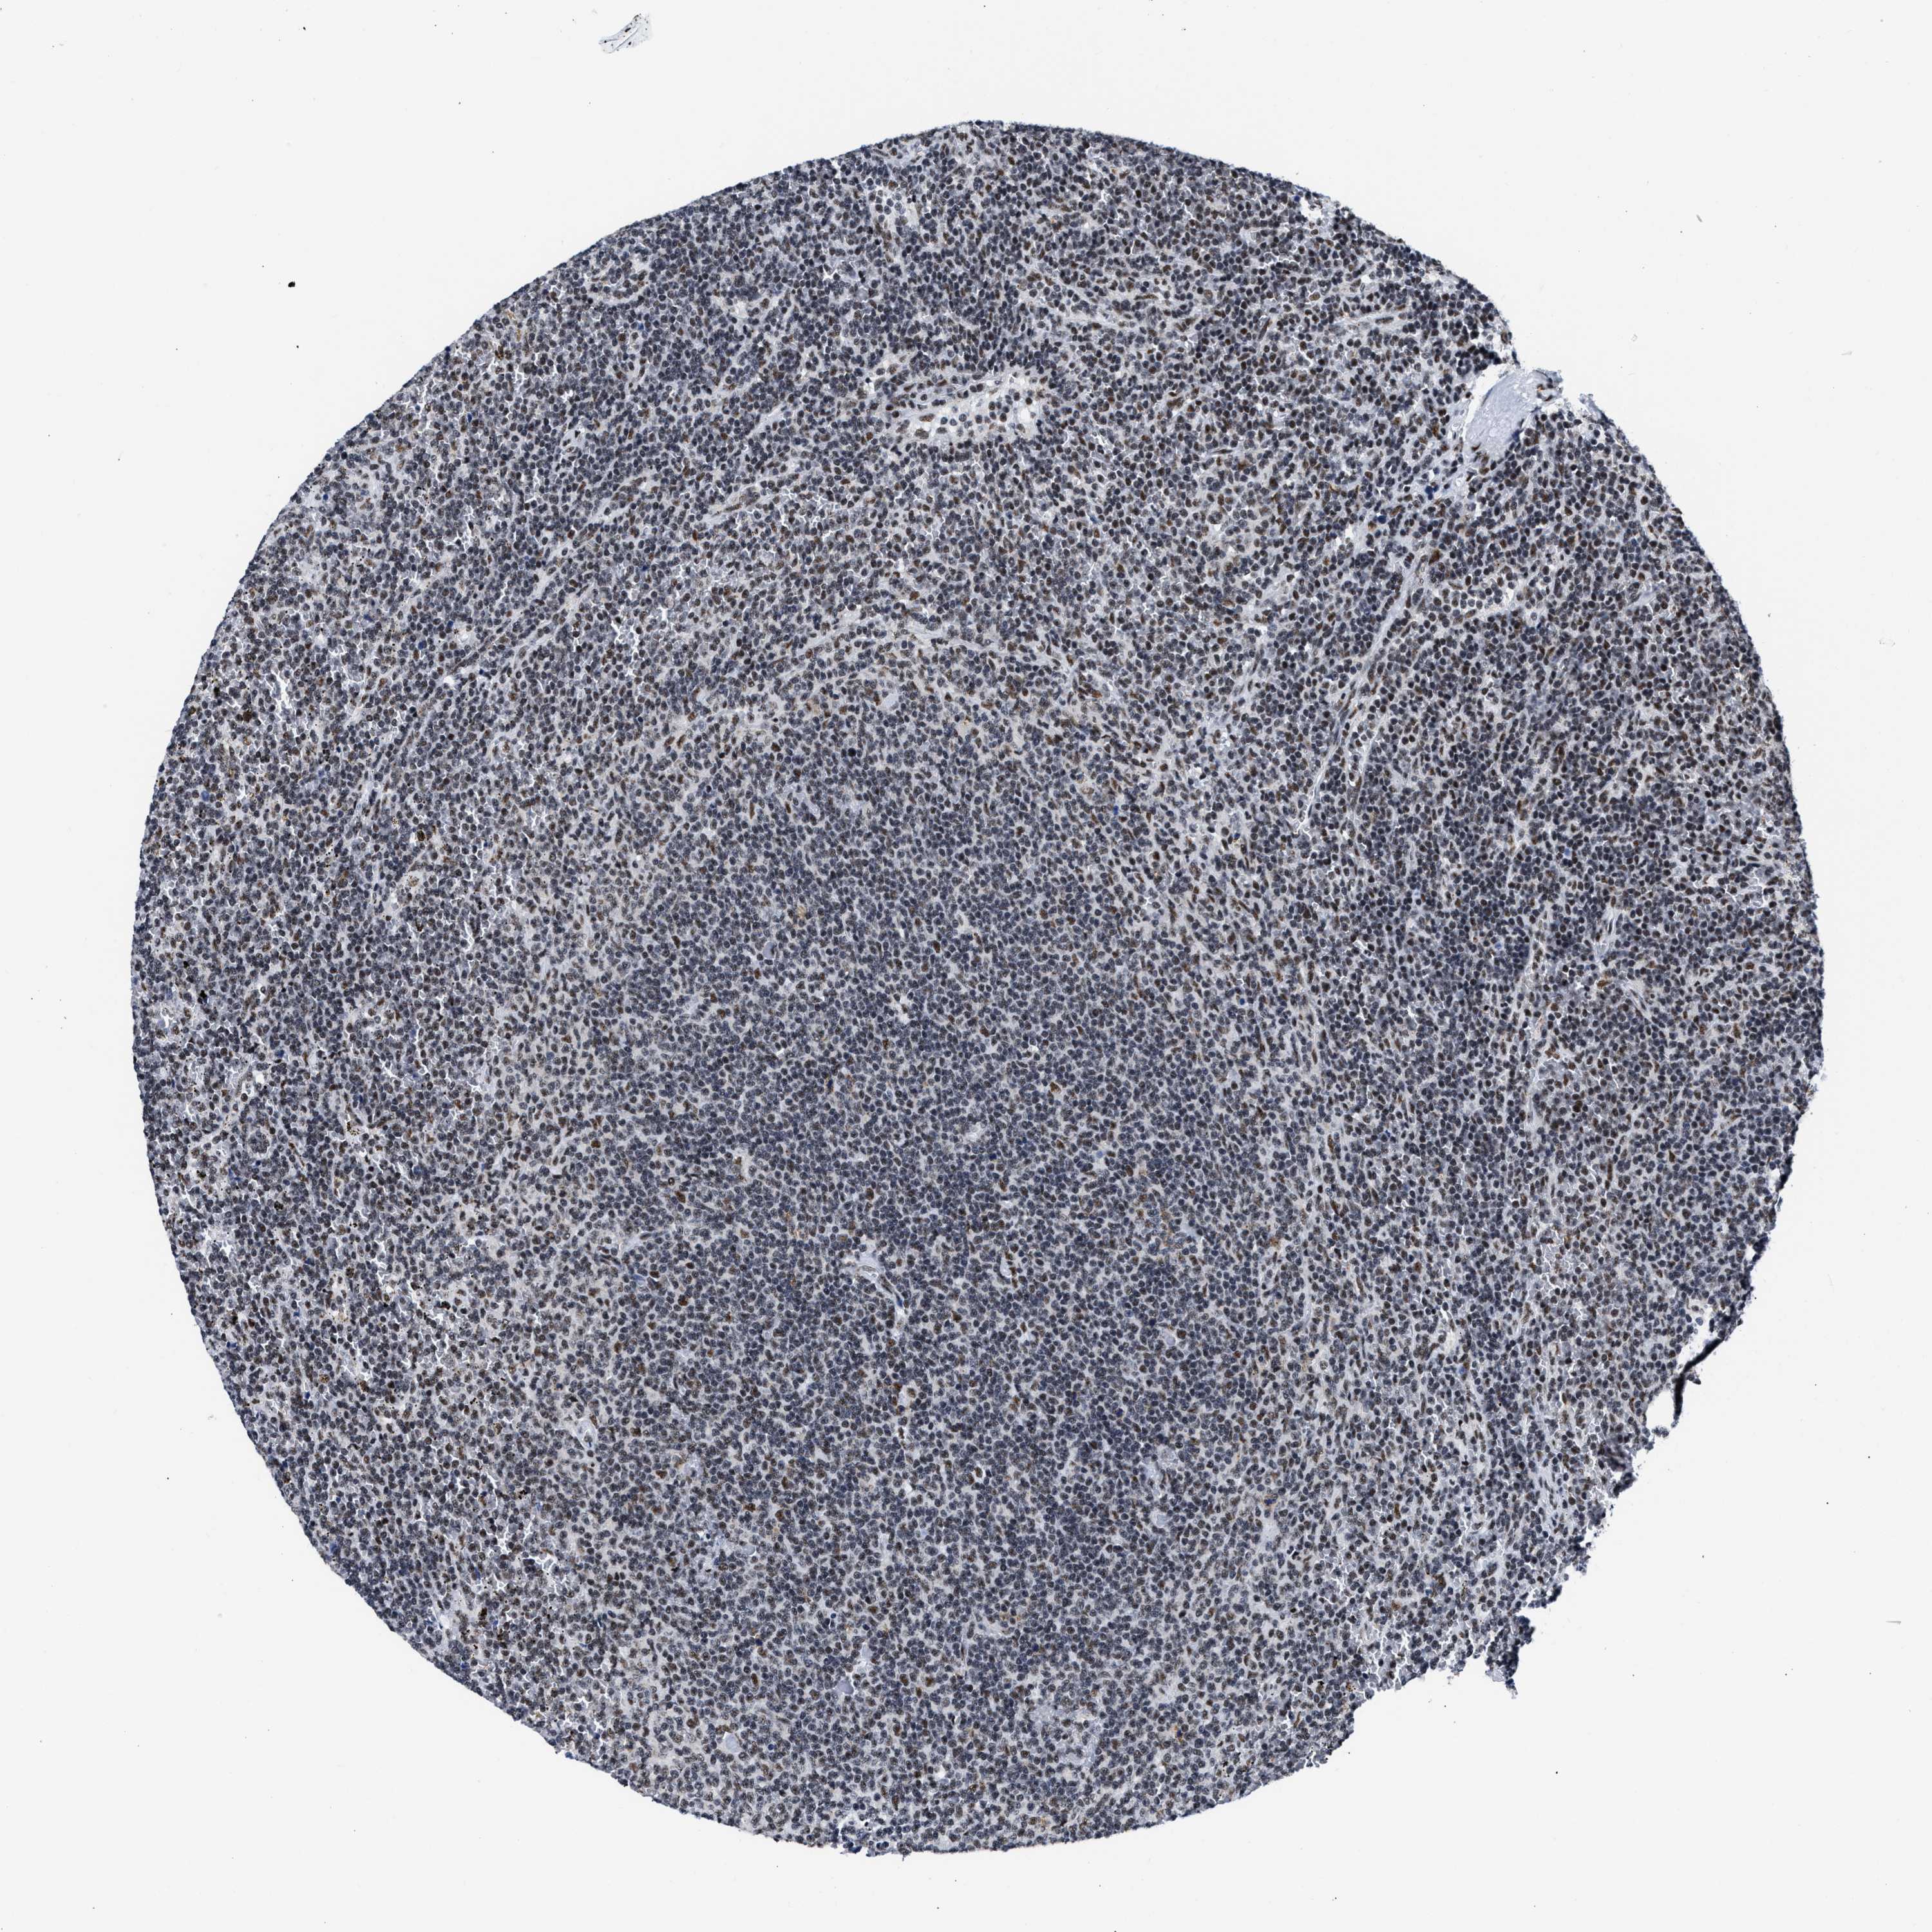

CANCER LYMPHOMA Show tissue menu

LYMPHOMA - Protein expressioni

A mouse-over function shows sample information and annotation data. Click on an image to view it in a full screen mode. Samples can be filtered based on level of antibody staining by selecting one or several of the following categories: high, medium, low and not detected. The assay and annotation is described here.

Antibody stainingi

Antibody staining in the annotated cell types in the current human tissue is reported as not detected, low, medium, or high, based on conventional immunohistochemistry profiling in selected tissues. This score is based on the combination of the staining intensity and fraction of stained cells.

Each image is clickable and will lead to virtual microscopy that enables deeper exploration of all samples and also displays staining intensity scores, fraction scores and subcellular localization as well as patient and tissue information for each sample.

Antibody HPA018403

Staining

Low

Intensity

Weak

Quantity

<25%

Location

Nuclear

Hodgkin's disease, NOS

Malignant lymphoma, non-Hodgkin's type, High grade

Malignant lymphoma, non-Hodgkin's type, Low grade